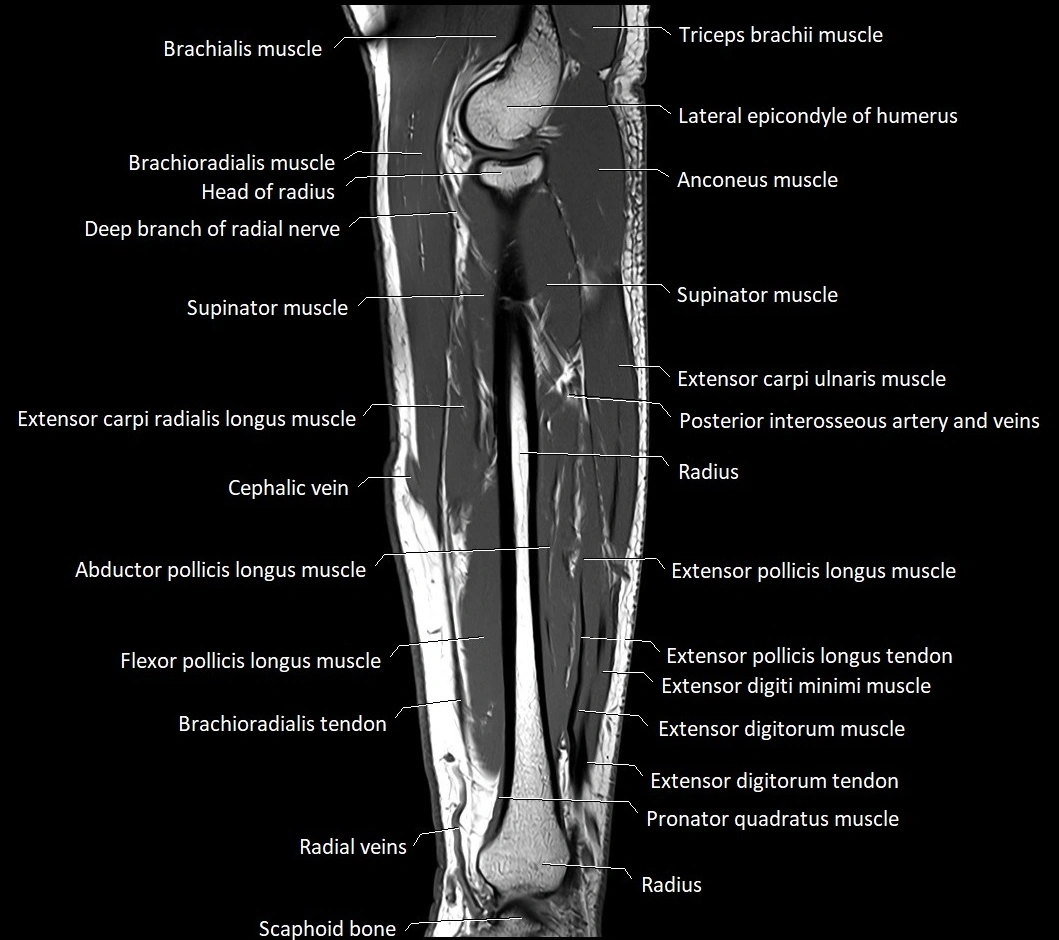

MRI images

image